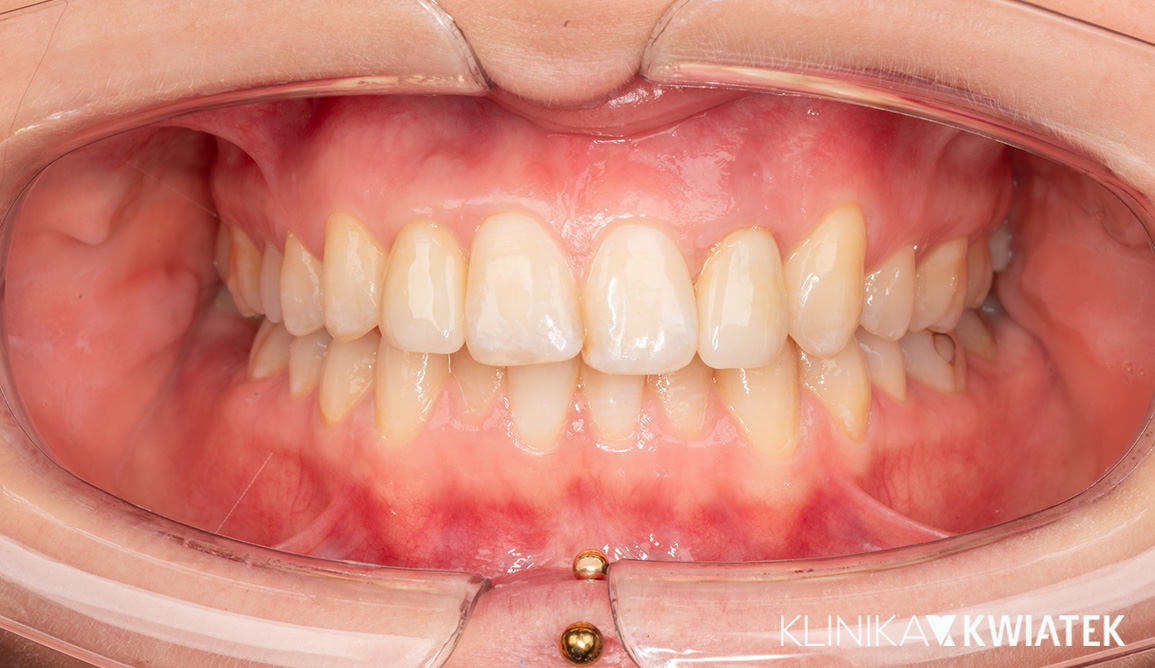

Kliniczna precyzja i estetyka – jak przywróciliśmy funkcję i piękno uśmiechu

Pacjentka zgłosiła się z wadą zgryzu, licznymi ubytkami i utraconymi zębami trzonowymi, co powodowało trudności w żuciu i estetyczne niezadowolenie. Leczenie obejmowało ekstrakcje, ortodoncję, implantację oraz kompleksową rekonstrukcję protetyczną. Po kilkunastu miesiącach terapii Pacjentka odzyskała pełną funkcję zgryzu i piękny, harmonijny uśmiech.